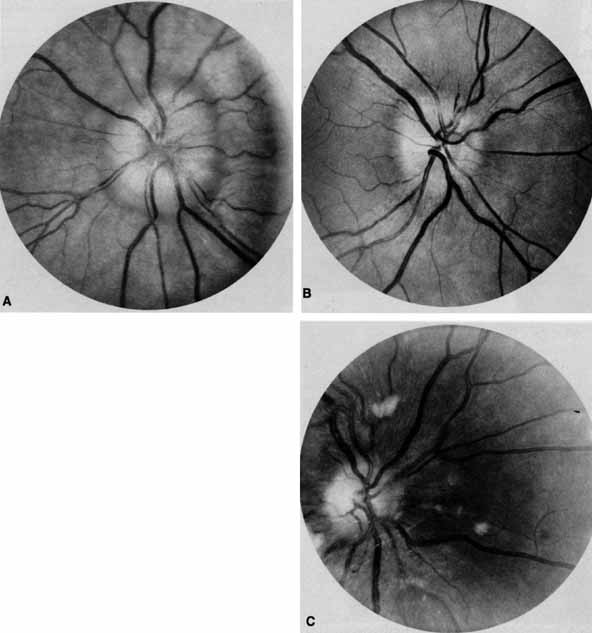

OPTIC NERVE The tempo and character of vision loss can be important diagnostically. The tempo of visual acuity deterioration varies from optic nerve tumors with characteristically chronic and progressive loss to that of cellulitis or idiopathic orbital inflammation which may be apoplectic. Characteristics of visual change are also important; for instance, gaze-evoked vision loss is most commonly associated with intraconal tumors such as [MT1]optic nerve meningiomas or cavernous hemangiomas.6 This symptom may also occur in patients with orbital fractures, intraconal foreign bodies, or extraconal tumors that compress the central retinal artery.7,8 Transient obscurations of vision, a fleeting blurring of vision lasting seconds, may be associated with papilledema.9 This symptom can be differentiated from amaurosis fugax (complete loss of vision of moderate duration), which is more likely to be secondary to embolic occlusion of the ophthalmic or central retinal artery.10 Every patient with a suspected orbital abnormality deserves a complete eye examination, whether he or she needs it or not.11 Visual acuity with current correction, a manifest refraction, and a cycloplegic refraction are important to detect induced hyperopia from an intraconal tumor. A rough approximation is 3 D of induced hyperopia for each millimeter of globe shortening. Evaluation of afferent visual function should include tests of color vision, relative afferent pupillary defect, and visual field. Ophthalmoscopy can be very helpful in orbital diagnosis. Optic disc edema may be caused either by papilledema (increased intracranial pressure) (Fig. 11A), papillitis (anterior optic neuritis) (Fig. 11B), or vasculitis (e.g., lupus erythematosus, sarcoidosis, Wegener's granulomatosis, and giant cell arteritis) (Fig. 11C).12 Papilledema (Fig. 11A) is usually present with near-normal visual function, although some patients may lose vision.9 In contrast, papillitis (Fig. 11B) characteristically leads to reduced visual function, commonly is associated with orbital pain, and is associated with inflammatory cells in the vitreous overlying the disc. Optic disc vasculitis (Fig. 11C) may be present with other findings of vasculitis, and commonly is associated with poor acuity and evidence of vascular occlusion (e.g., cotton-wool spots, hemorrhages). The differential diagnosis of the swollen, erythematous disc is discussed elsewhere in these volumes. Optociliary shunts (Fig. 12A) develop as a result of long-term obstruction of the central retinal vein. This may occur secondary to optic nerve meningiomas,13 optic nerve gliomas,14,15 optic nerve meningoceles,16 central retinal vein occlusions,17 optic nerve sarcoidosis,18 craniosynostosis,19 optic nerve arachnoid cysts,20 optic disc drusen,21 and papilledema.15 Congenital optociliary shunts, which are exceedingly rare, have not been associated with optic neuropathy or orbital disease.22,23 The presence of optic nerve pallor, poor acuity and optociliary shunts generally implies an optic nerve meningioma in the absence of other funduscopic findings (Fig. 12B).13 Visual field testing can also be helpful in diagnosis of orbital processes. Optic disc–associated visual field changes are usually altitudinal because of the structure of the horizontal raphé (Fig. 13). This visual field defect is typically a result of anterior ischemic optic neuropathy (AION).24 Compressive lesions of the orbit or retrobulbar inflammation are more likely to produce a central or cecocentral scotoma. However, one must be aware that there is a significant degree of overlap between various types of optic nerve lesions and visual field abnormalities.25 In these cases, neuroimaging may be a useful adjunct in differentiating between different neuro-ophthalmic and orbital processes.26 The relationship of visual function to orbital findings often helps in the differential diagnosis. For instance, patients with cavernous hemangiomas may have significant proptosis but retain normal, best-corrected visual function (see Fig. 7B), but patients with intrinsic optic nerve meningiomas may demonstrate minimal proptosis with significant vision loss (see Fig. 12B). Trigeminal Sensation Historically, the progression of numbness may be helpful in diagnosis of orbital disease. For instance, adenoid cystic carcinoma of the lacrimal gland27,28 and some melanomas29 have a predilection for perineural invasion. The presence of a lacrimal gland mass, which is followed by numbness in the distribution of the lacrimal (see Fig. 2), zy-gomaticotemporal, or zygomaticofacial nerves (Fig. 9), can indicate perineural extension of an adenoid cystic carcinoma. Corneal sensation should always be tested prior to anesthetizing the cornea for applanation tonometry. Corneal sensation can be roughly quantified using an anesthesiometer; however, asymmetry of corneal sensation may be the most important finding in unilateral orbital disease. A cotton wisp, pulled from a cotton-tip applicator, is lightly drawn from the conjunctiva across the limbus onto the cornea. The blink should occur with corneal but not conjunctival touch. Sensory testing of cranial nerves V1 and V2 with the cotton wisp can be performed at the same time. The cutaneous distribution of the zygomaticofacial and zygomatico-temporal branches should not be ignored (see Fig. 9). The upper teeth should also be tested by tapping with the cotton-tip applicator stick, comparing right to left sides and the front teeth to the molars. Blowout fractures that involve the infraorbital nerve commonly result in numbness of the upper teeth because the anterior and middle superior alveolar nerves arise from the infraorbital nerve within the infraorbital canal (see Fig. 10). However, because the posterior superior alveolar nerve arises from the infraorbital nerve before it enters the infraorbital canal, if the molars are also numb, one must consider the possibility of an associated basilar skull fracture. Pain is a helpful diagnostic symptom. There are five types of pain associated with the eye and orbit11,19,30: